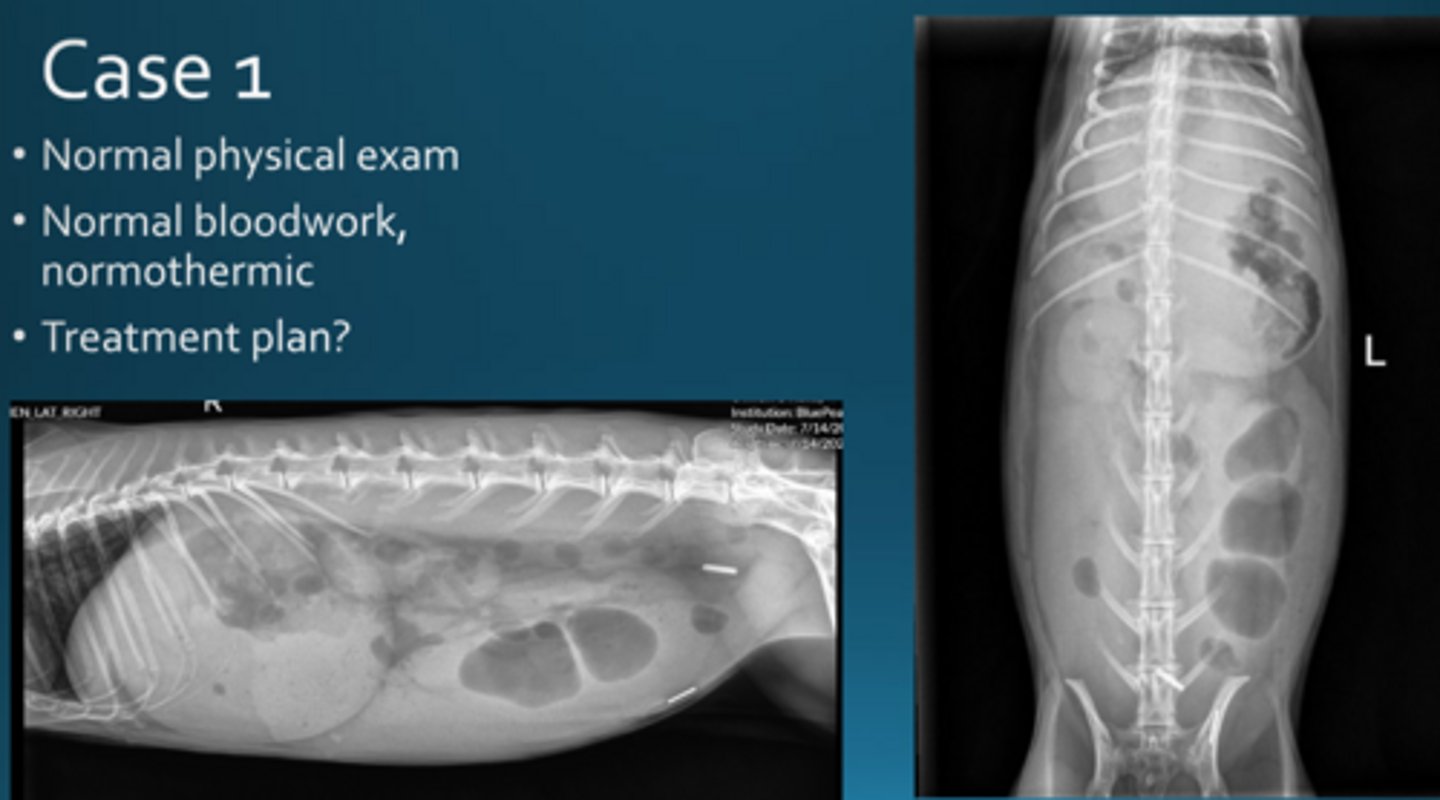

There is lots of gas in the cecum and the stomach is getting large.

Give IV fluids, syringe feed, lidocaine CRI

What do you want to do for this rabbit, who has recently been spayed?

Hyperglycemia associated with GI obstruction. This patient is also hypothermic.

Give thermosupport, surgery, may sedate and pass orogastric tube to relieve pressure in stomach

This rabbit has a temperature of 98.1 F. There is a firm, cranial abdominal mass. The bloodwork is normal apart from hyperglycemia of 641. What is likely happening here and how do you treat?